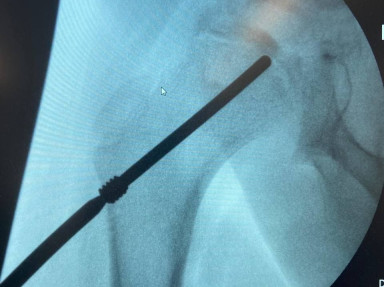

Специалисты Самарской областной детской клинической больницы имени Н.Н.Ивановой впервые выполнили операцию по имплантации инновационного медицинского устройства — ортопедического электрета.

Уникальная операция проведена 9-летнему мальчику с болезнью Легга-Кальве-Пертеса. Это тяжелое инвалидизирующее заболевание, приводящее к асептическому некрозу головки бедренной кости. У ребенка были такие симптомы как хромота и боль. Традиционное лечение таких заболеваний предполагает многолетнюю (до 5 лет) разгрузку сустава с использованием костылей, иммобилизацию или сложные операции.

✔️"Имплантация инновационного устройства, приобретенного для ребенка при содействии благотворительного фонда и министерства здравоохранения региона, должен уменьшить продолжительность заболевания и, как следствие, снизить тяжесть течения патологического процесса" - рассказал главный внештатный детский травматолог-ортопед министерства здравоохранения Самарской области, врач-травматолог-ортопед детской больницы имени Ивановой Павел Рыжов. - Ортопедический электрет — это российская разработка, представляющая собой имплантируемое устройство для постоянной электростимуляции процессов в костной и хрящевой ткани. Имплантат создает вокруг пораженного сустава постоянное электрическое поле, которое активирует естественные восстановительные механизмы организма, уменьшает воспаление и отек. Это способствует сокращению сроков лечения".